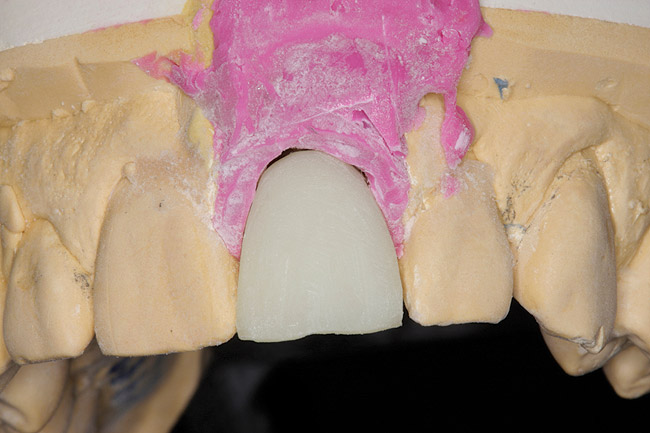

The restorative dentist can duplicate the contours of the extracted tooth for the new screw-retained provisional following these instructions: First make an index of implant position with a transfer coping. Then, either pour up a working cast or alter the cast used to fabricate the surgical guide. The cast is altered in the area of the implant fixture to allow the indexed transfer coping to seat with the appropriate analog attached (Figure 2).

Fig 2. Cast altered so indexed transfer coping can seat with appropriate analog attached.

Figure 2